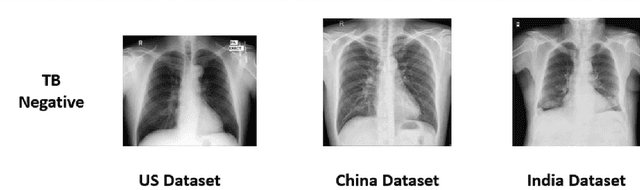

Abstract:We demonstrate that Domain Invariant Feature Learning (DIFL) can improve the out-of-domain generalizability of a deep learning Tuberculosis screening algorithm. It is well known that state of the art deep learning algorithms often have difficulty generalizing to unseen data distributions due to "domain shift". In the context of medical imaging, this could lead to unintended biases such as the inability to generalize from one patient population to another. We analyze the performance of a ResNet-50 classifier for the purposes of Tuberculosis screening using the four most popular public datasets with geographically diverse sources of imagery. We show that without domain adaptation, ResNet-50 has difficulty in generalizing between imaging distributions from a number of public Tuberculosis screening datasets with imagery from geographically distributed regions. However, with the incorporation of DIFL, the out-of-domain performance is greatly enhanced. Analysis criteria includes a comparison of accuracy, sensitivity, specificity and AUC over both the baseline, as well as the DIFL enhanced algorithms. We conclude that DIFL improves generalizability of Tuberculosis screening while maintaining acceptable accuracy over the source domain imagery when applied across a variety of public datasets.